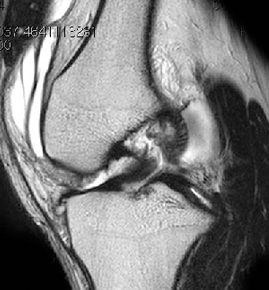

• ACL 손상 방사선 사진4